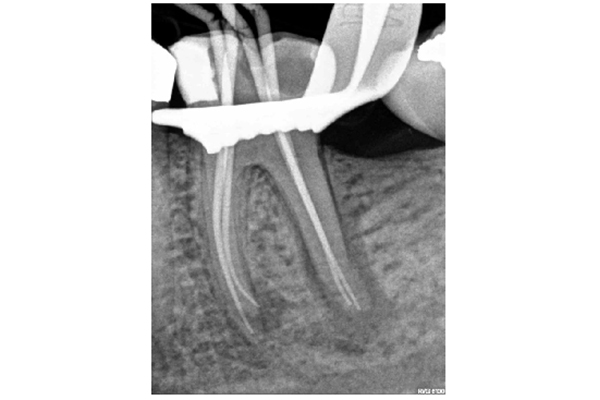

The narrowest part of the canal is the apical constriction or minor foramen. From this point the canal gradually widens to terminate at the apical foramen or major foramen (Figure 1).

- The apical foramen is not always located at root terminus (Figures 1 and 2). There can be up to 3mm variation in 50-98% of roots. It is generally greater in posterior teeth

Figure 2a: Master cone radiograph. The apical foramen exits the root laterally on the mesial root. An apex locator is essential in these cases to determine the WL. b) Mid-fill radiograph - The distance between with apical constriction and root terminus increases with age due to secondary cementum deposition at the root apex (Figure 1)